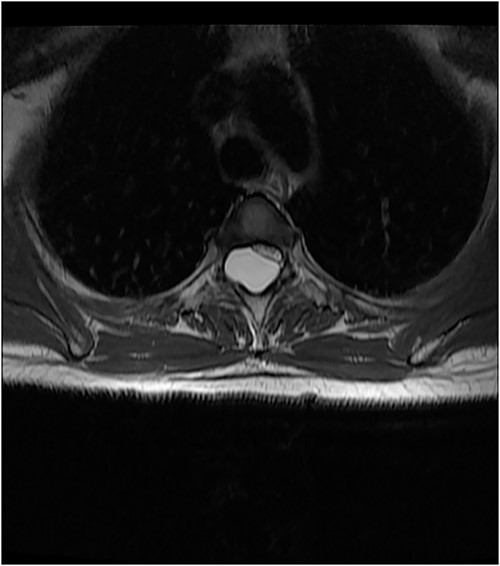

On the first postoperative day, neurological examination revealed that power had returned to the preoperative state and her pain had significantly reduced. She was commenced on physiotherapy and on the third day postop, her limb pain had completely disappeared, while power had improved to 4 in the right lower extremity muscle groups. She was discharged on the fifth postoperative day and was to be seen in the out-patient clinic. Postop images showed total resection of cyst and gradual re-expansion of the spinal cord (Fig. 6). At 12-week follow-up, she had complete resolution of her preoperative symptoms and had returned to full functional independence.